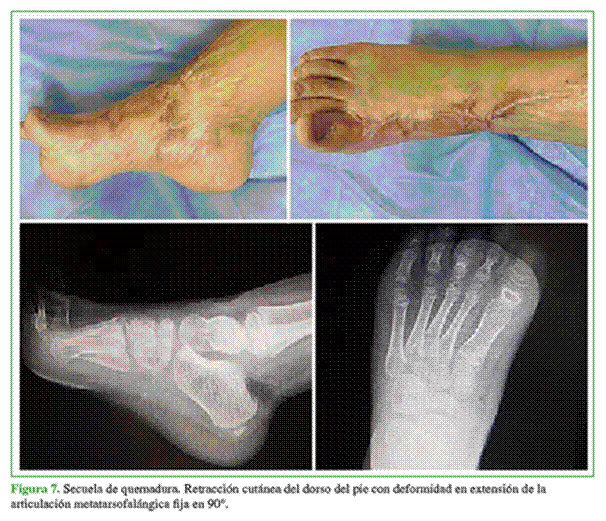

Niña de 5 años, que tiene una secuela de quemadura con agua hirviendo en el dorso del pie derecho con retracción cutánea y deformidad del hallux en extensión fija a 90°, de tres años de evolución. Fue sometida a múltiples Z-plastias y correcciones sin buen resultado. Desde hace 30 meses, la paciente no puede colocarse un calzado debido a la deformidad residual (Figura 7).